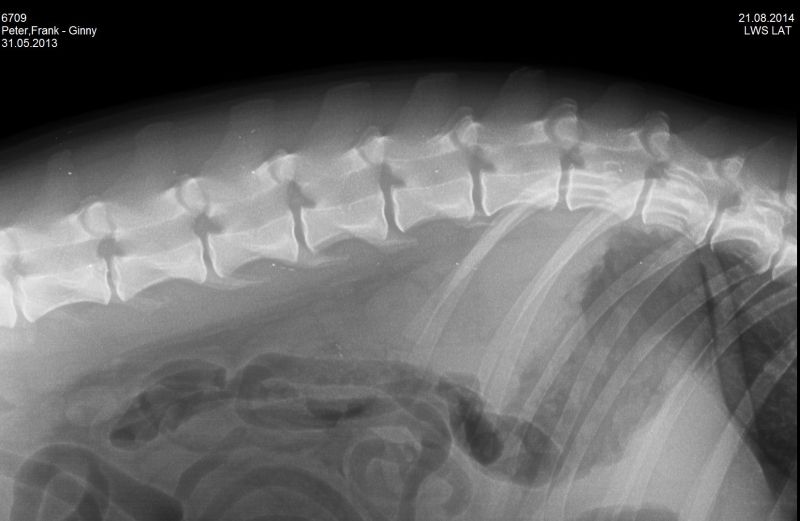

21.08.2014 - Ginny HD-und ED geröntgt - 15 Monate alt

24.08.2014 - Ginny - 15 Monate alt